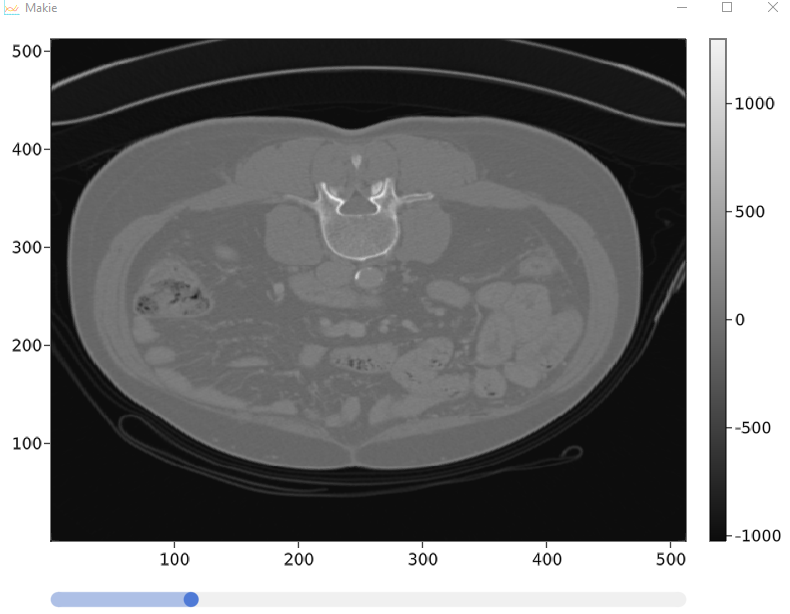

可以工作但没有这两个功能的代码以及它的外观

我使用makie.jl和slicesNumb进行PET/CT扫描的可视化,我有三维衰减值阵列,我用滑块显示热图和改变切片--这很好,我有两个问题。

function singleCtScanDisplay(arr ::Array{Number, 3})

fig = Figure()

sl_x = Slider(fig[2, 1], range = 1:1:size(arr)[3], startvalue = 40)

ax = Axis(fig[1, 1])

hm = heatmap!(ax, lift(idx-> arr[:,:, floor(idx)], sl_x.value) ,colormap = :grays)

Colorbar(fig[1, 2], hm)

fig

end